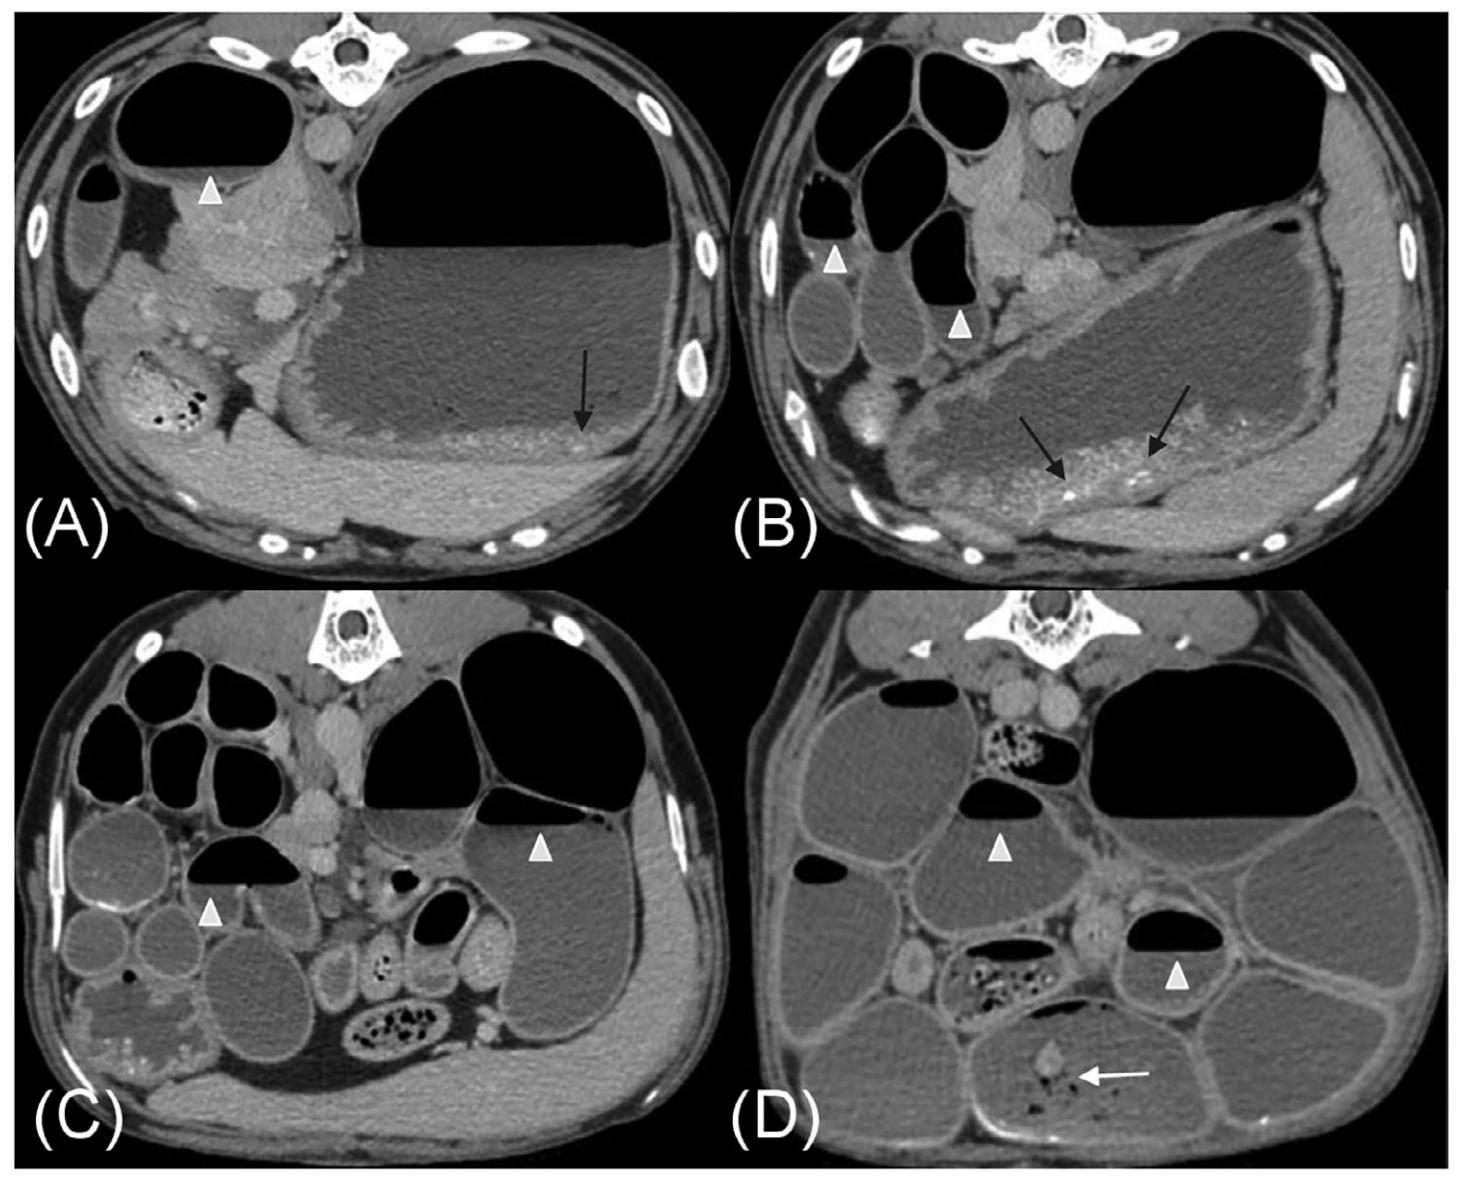

腹部CT显示胃中度扩张,内含气体、不均匀软组织和颗粒状矿物质,小肠严重弥漫性扩张(约为L5高度的4倍),肠腔内充满液体、气体以及不同量的颗粒状矿物质和不均匀软组织。小肠内液体和气体分层,形成水平的气液界面,提示蠕动减少或缺失(下图)。小肠内的颗粒状矿物质和不均匀软组织未占据整个肠腔,未被视为梗阻性病变,因此影像学诊断为弥漫性功能性肠梗阻

胃肠道壁厚度均匀,未见异常肠壁增厚或对比增强改变。CT血管造影的所有阶段均显示正常血管增强,排除了血栓栓塞性疾病或肠系膜扭转/肠扭转作为引起广泛严重肠梗阻的原因。未发现腹膜病变。

↑ 对比后静脉期CT图像,显示正中矢状面(A)、左侧旁矢状面(B)和背平面(C)。在AB中,头部在左侧,在C中,头部在上方。大部分小肠中度弥漫性扩张,内含均匀软组织和气体的混合物,形成依赖重力的气液界面(白三角)。几个小肠段内有少量不均匀的软组织、矿物质和气体衰减物质,但未完全充满肠腔(白箭头)。在A中,腹腔动脉和肠系膜上动脉有正常的对比剂充盈(*)。

↑ 横断面对比后静脉期CT图像,所有图像中均可见中度胃和小肠扩张。X光检查中发现的胃内颗粒状矿物质仍然存在(黑箭头)。大部分小肠段内均匀软组织和气体的分层,形成依赖重力的气液界面(白三角)。几个小肠段内有少量颗粒状矿物质和不均匀软组织,但未完全充满肠腔(白箭头)。胃和小肠的肠壁厚度及对比增强均正常。